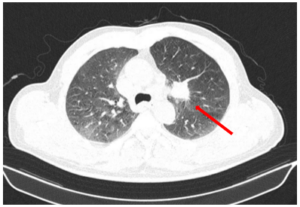

Ca lâm sàng: Kết hợp thuốc miễn dịch (Pembrolizumab) với hóa chất trong điều trị ung thư phổi không tế bào nhỏ di căn tại bệnh viện Bạch Mai.

Ca lâm sàng: Kết hợp thuốc miễn dịch (Pembrolizumab) với hóa chất trong điều trị ung thư phổi không tế bào nhỏ di căn tại bệnh viện Bạch Mai. GS.TS. Mai Trọng Khoa1,2, PGS.TS. Phạm Cẩm Phương1,2, BSCKII. Lê Viết Nam1, SV. Đào Phương Thúy2. 1: Trung tâm Y học...